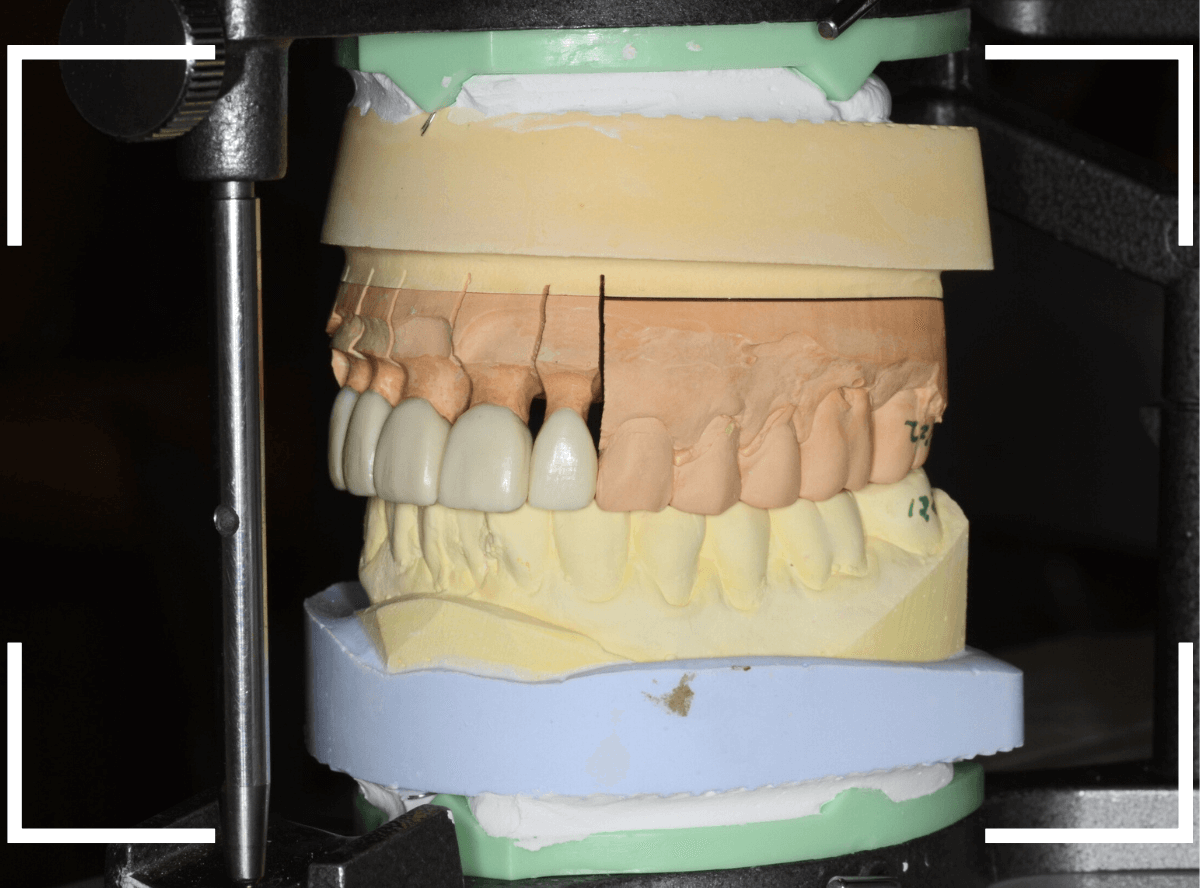

手前の3本のメタル・コアも審美性の高いファイバー・コアに入れ替えて、全体の形態をトリミングします。

今回のように、本数が多い時、精密性が求められる時などは、いきなり仕上げをせずに、ジルコニアのフレームにワックスを盛った状態で、お口の中に試適してフレームの適合や患者さんに歯の外形のチェックなどをしてもらいます。

試適で患者さんにも確認がとれましたので、表面をセラミックで最終仕上げをします。

微調整をして最終setをしました。

患者さんにも満足していただける仕上がりになりました。

今回はこちらでは割愛したメタル・コアの除去に時間がかかっている事や仮歯の製作・調整などがあり、回数と期間のかかる治療になりました。

本数の多いセラミック治療は治療・調整箇所などが多くなりますので、治療回数と期間に余裕をいただいています。